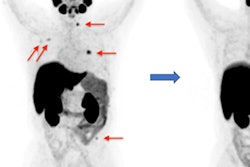

A 72-year-old patient with a prostate-specific antigen (PSA) level of 50.8 ng/ml. The lesion with tumor diameter of 11.7 mm (arrow) was evaluated as positive (PI-RADS score 4) on bpMRI with T2WI image (A), DWI image (B), and ADC map (C), indicating prostate cancer lesion. On F-18 PSMA-1007 PET image (D), the lesion showed intense uptake with an SUVmax of 79.6 (PSMA-RADS score 5). Combined with bpMRI and PET score, fused F-18 PSMA-1007 PET/MRI image (E) further suggested prostate cancer. Subsequent biopsy results (F) proved prostate cancer lesion of ISUP grade 5 with Gleason score 5+4. Image courtesy of Prostate International.Out of the 48 suspected prostate cancer lesions in 29 patients, 38 were identified with biopsies as clinically significant prostate cancer, and 10 were noncancerous lesions. Against these pathological results, F-18 PSMA-1007 PET/MRI demonstrated much greater diagnostic accuracy (area under the curve [AUC]), sensitivity, specificity, positive predictive value (PPV), and negative predictive value (NPV) than bpMRI, the researchers found.